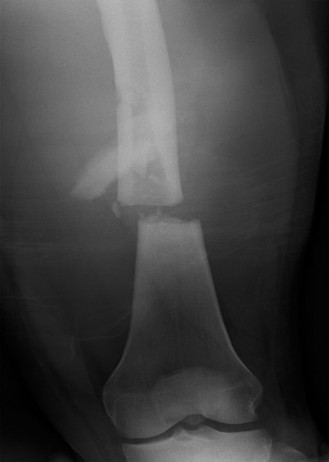

A 16-year-old male is brought to the emergency department after a reported gunshot injury. He has a wound to …